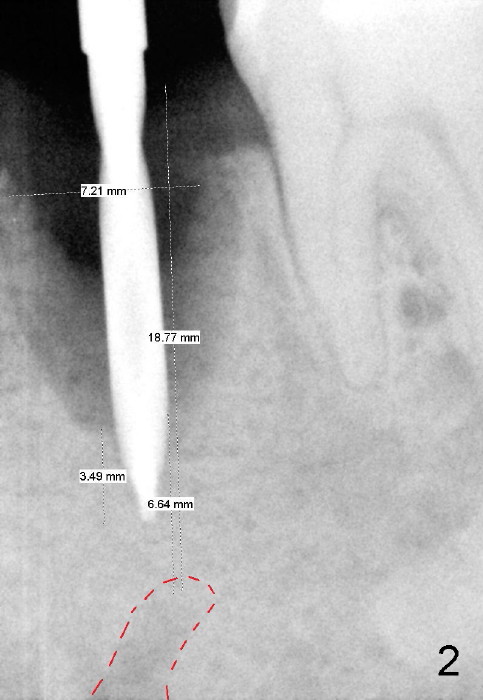

To avoid injury to the mental loop (Fig.2 dashed line), the depth of initial osteotomy is tightly controlled apical to the bottom of the socke. Accurate measuring is the 2nd important measure to assure no or minimal neurological trauma. The wide socket (due to infection) allows to place an implant as wide as 7 mm.